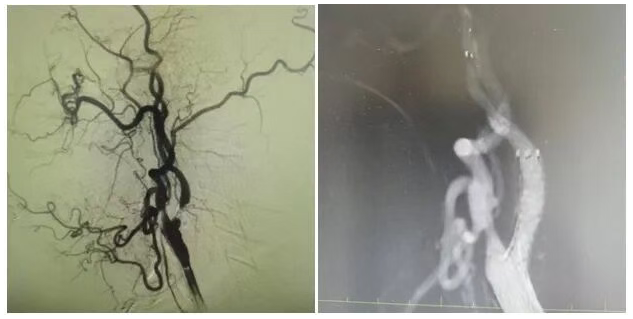

为明确病因,团队为姜大爷安排针对性检查:头颅 MRI 弥散成像显示左侧大脑半球有分水岭性脑梗死,提示脑组织缺血损伤,颈部 MRA 检查发现左侧颈内动脉起始处重度狭窄,血流信号减弱。随后的 DSA(数字减影血管造影)检查进一步明确,左侧颈内动脉起始处狭窄程度超 90%,呈 “闭塞前改变”,血流受阻导致左侧大脑半球供血不足,进而引发脑梗死与抽搐。

手术当天,丁金明主任亲自操刀,团队默契配合:在姜大爷右侧腹股沟穿刺股动脉置入动脉鞘,沿鞘送导丝和导管,在 DSA 引导下穿过狭窄部位,用球囊预扩张后,精准释放颈动脉支架。术后 DSA 显示左侧颈内动脉血流通畅,狭窄解除。手术历时 1 小时,姜大爷生命体征平稳,无并发症。